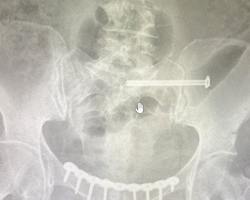

В ходе обследования врачи диагностировали сочетанную травму — разрыв лонного и крестцово-подвздошного сочленений, которые соединяют различные кости таза и играют важную роль в поддержании вертикального положения тела и распределении нагрузки. Было принято решение провести хирургическое лечение.

— Мы выполнили остеосинтез, то есть соединили обломки костей. Чтобы правильно их закрепить использовали специальные пластины и винты. В последующем их не потребуется удалять. И пластина, и винты из титана — биосовместимого материала, который не вызывает негативных реакций со стороны организма, и никак не помешает пациентке, — рассказал травматолог-ортопед Чеховской больницы Салман Асламханов.